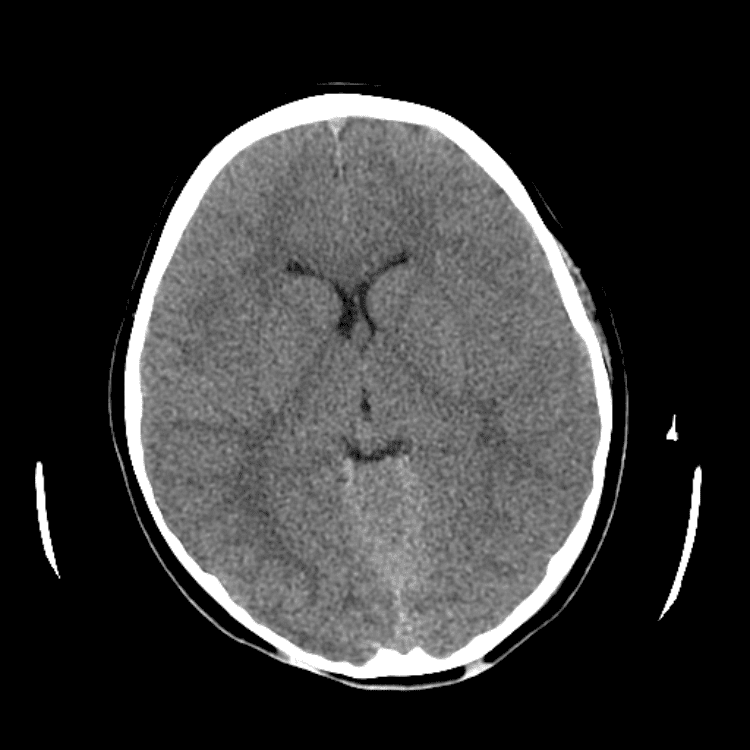

Nontraumatic Brain

Classic